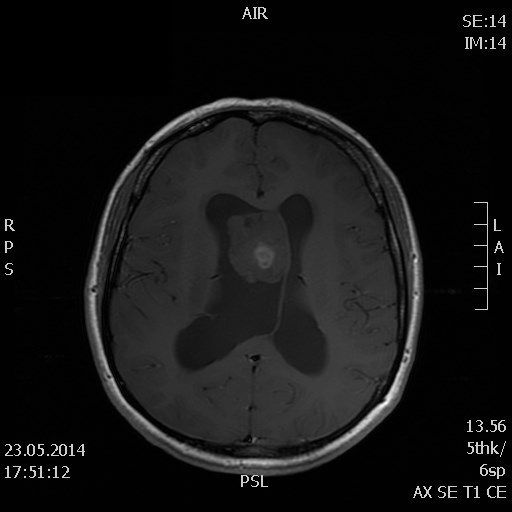

Хірургічне лікування внутрішньомозкових пухлин

Провідним методом для лікування внутрішньомозкових церебральних новоутворень залишається їх хірургічне вилучення. У нашому відділенні вилучення пухлин головного мозку проводиться під операційним мікроскопом, із застосуванням мікроінструментарію, багатофункціонального електрокоагулятора, медичного рубінового лазера.

Доброякісні внутрішньомозкові новоутворення півкуль головного мозку, як правило, можуть бути видалені в повному обсязі, тобто радикально, за умови, що пухлина не знаходиться у функціонально важливій, і, або глибинній зоні й ризик її повного видалення не переважає очікуваного позитивного ефекту в аспекті виживання і якості життя пацієнта після операції.

Тотальне видалення злоякісних гліальних пухлин мозку найчастіше неможливо у зв’язку з їх значним проростанням в навколишню мозкову тканину, ризику пошкодження життєво важливих зон мозкової тканини та кровоносних судин.